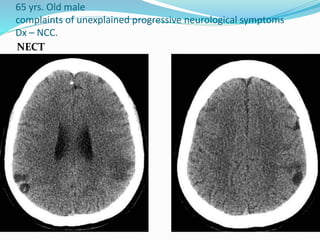

65 yrs. Old male

complaints of unexplained progressive neurological symptoms

Dx – NCC.

NECT